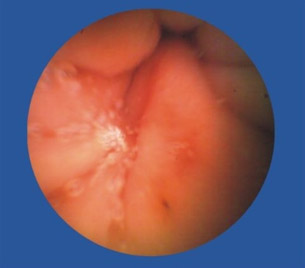

口服后借助消化道蠕动使之在消化道内运动,从食道→胃→十二指肠→小肠→结肠→直肠的方向运行探测,胶囊内的摄像头像卫星扫描技术一样, 对经过的腔段进行连续摄像,以每秒两幅图像的拍摄频率,通过电磁信号被无线传输到病人随身携带的数码记录仪上。

OMOM胶囊内镜数码相机工作结束后,医生即可取下数据记录仪与影像工作站连接,下载数万张图像数据,能有效诊断整个消化道疾病, 更能探测到被称为胃肠检查盲区的“小肠”。在无线胶囊吞服8~24小时后,就会由患者的肠道自动安全排除体外。

便血,去做检查,痔疮、胃镜、纤维结肠镜都做后,的出结论——小肠流血,但结肠镜够不着,还是看不见在具体位置。因此,也算是体验了下高科技,胶囊内镜。试过后真是感叹,这玩意儿真厉害!比普通药丸子稍大,一喝水下去了。自动掉头,自动拍照,自动传输。拉出来后找护士要了些消毒药水洗了下,细细观察。发现镜头口径有点小最多1mm,确实是高科技,这么小的东西,包括了拍照(可能是2个小时内的连续拍照),无线信号传输,方向姿势控制等等,厉害。

近日,67岁的陈爷爷因为便血导致严重贫血,胃镜、肠镜都做了却查不出病因。被转送到四川肛肠医院后,陈爷爷本来以为要再接受一次痛苦的内镜检查,没想到,医生给出的检查方式却是要他吞下一颗“胶囊”,同时穿上一件连着各种数据线的背心。很快,医生就发现陈爷爷的小肠上面存在一个不断出血的溃疡,经过手术,医生终于治好了陈爷爷的“怪病”。陈爷爷吞下的其实是一种叫“OMOM胶囊内镜”的检查仪器,主要用于小肠疾病的排查。